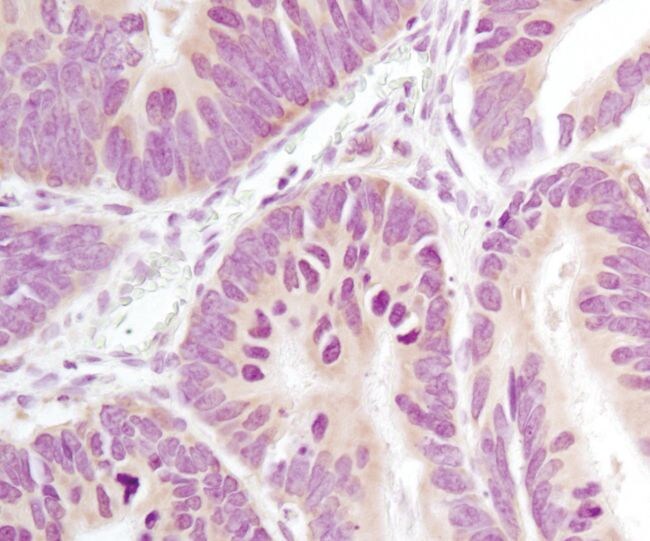

To address the need for quantitative colorimetric imaging, we have developed a method for analyzing histological samples on a high-content imaging instrument using a specialized brightfield unit

| Scientific poster (2016) | Incorporating histological analysis into existing high content imaging | antibodies, ArrayScan, brightfield microscopy, fluorescence microscopy/fluorescence imaging, high content analysis, immunohistochemistry (IHC) |